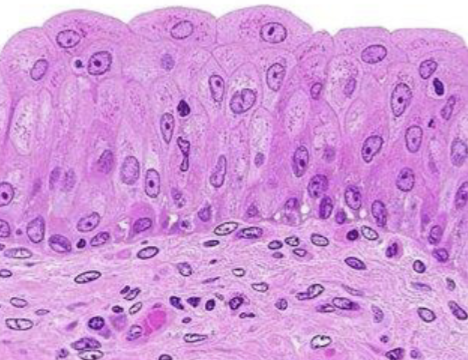

Clasifique tejido epitelial

urotelio

Indique sitio anatómico donde se encuentra

vejiga

Clasifique tejido epitelial

estratificado queratinizado

Indique sitio anatómico donde se encuentra

piel delgada

Forma de sus células

plano

Número de capas

estratificado

Indique función

protección